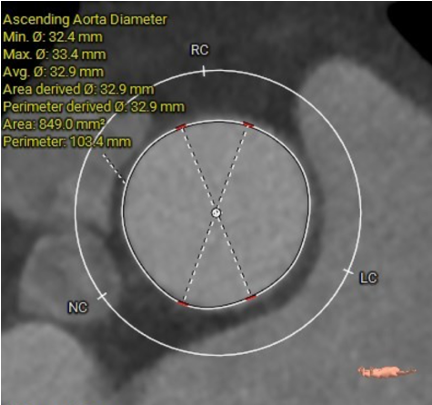

ASCENDING AORTA

CT数据显示该患者为Type1型主动脉瓣。